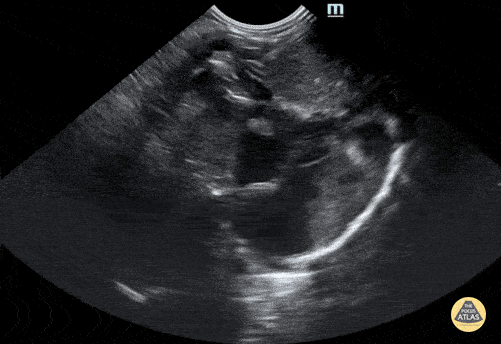

Normal neonatal subxiphoid view. Contributor: Jaron Smith, MD, Phoenix Children's Hospital

https://www.thepocusatlas.com/pedscardiac